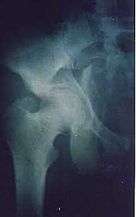

Acetabular fracture as seen on plain X-ray | |

Fractures of the acetabulum occur when the head of the femur is driven into the pelvis. This is caused either by a blow on the side or by a blow in the front of the knee, usually in a dashboard injury when the femur also may be fractured.[1]